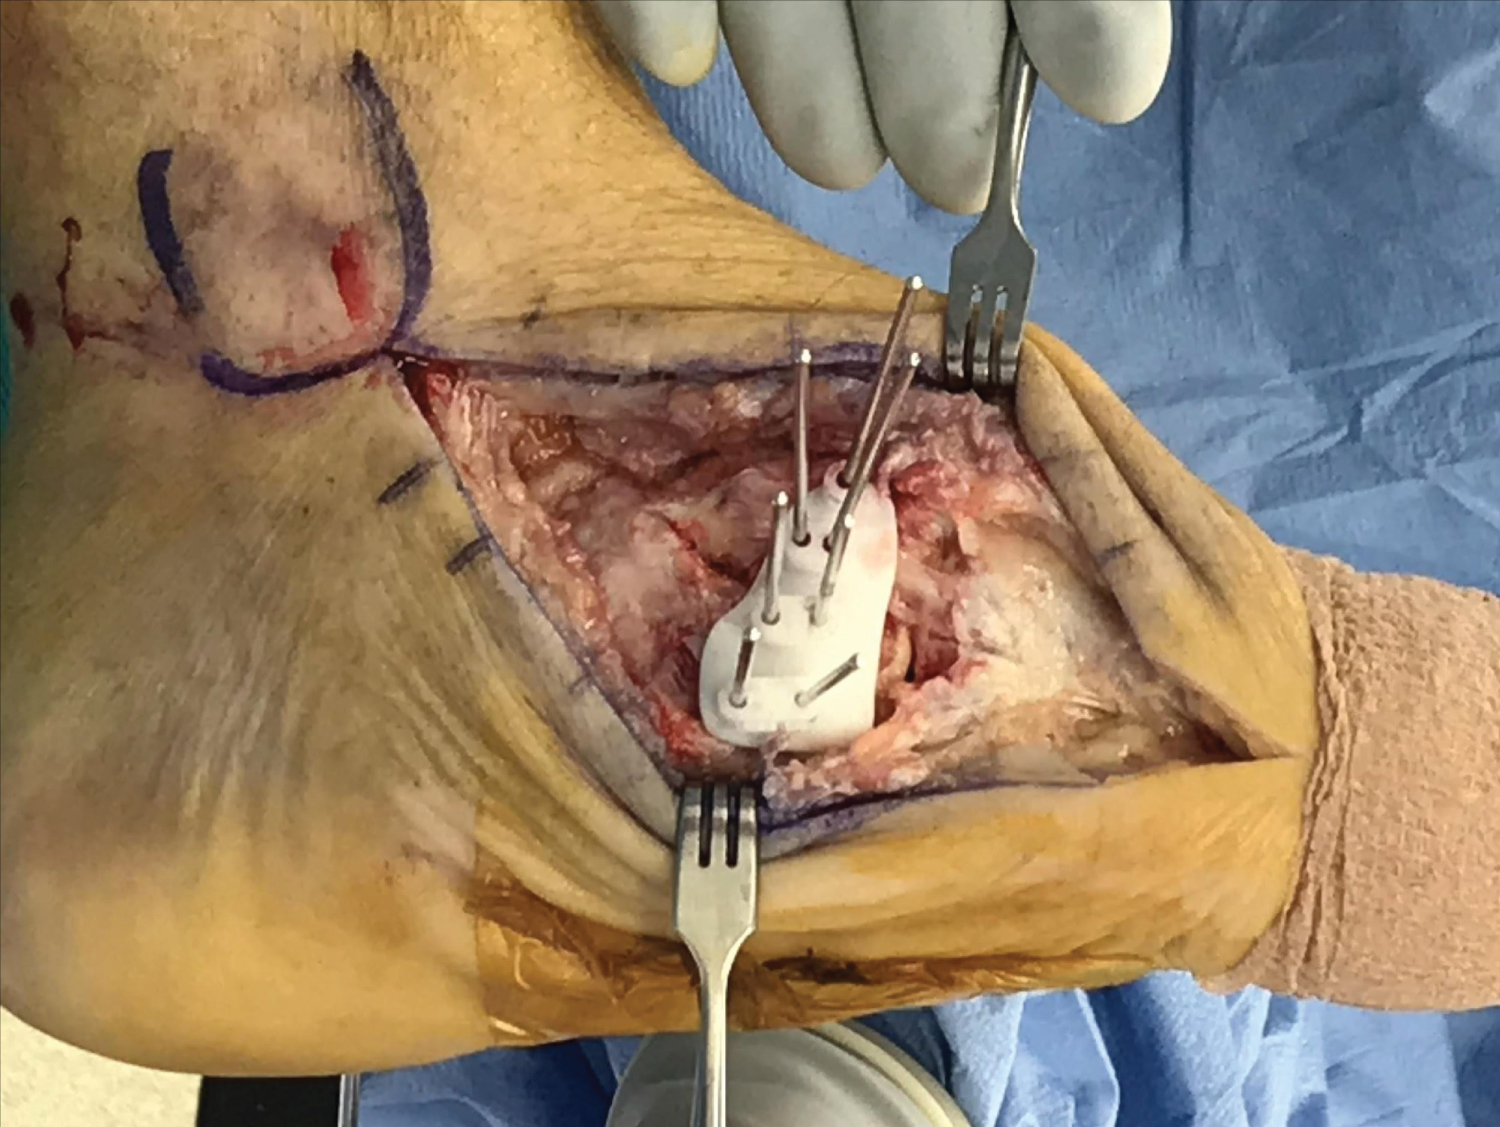

The guides can be placed along the model of the deformity to confirm where accurate placement of the guide should be. Once this is confirmed, the guide is fitted medially along the midfoot. An inherent "press-fit" should be appreciated. Two or three Kirschner wires are placed along the guide and placement is confirmed under fluoroscopy (Figure 4). The surgeon should note parallel placement of the wires indicating that placement is correct. Once this is confirmed, more wires can be placed along the cut guide to prevent movement.

Figure 4: Wedge resection based on cut-guide. View Figure 4